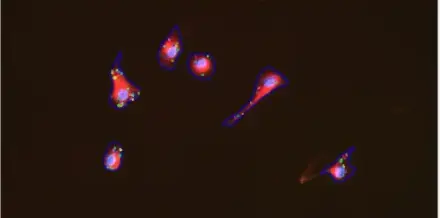

Cell Apoptosis

Cell Count

Cell Morphology

Cell Proliferation

Live/Dead for Cell Viability

Neurite Outgrowth

Nuclei & Mitochondria

Nuclei